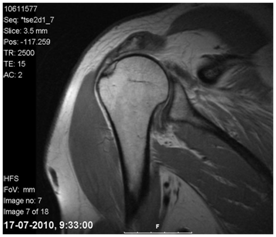

Imaging studies play a key role in both diagnosis and treatment selection, with the most commonly used imaging tests being Ultrasound and Magnetic Resonance Imaging.2 Magnetic resonance imaging has a sensitivity of about 100% in the diagnosis of coifera ruptures, allowing an accurate estimation of the size and patterns of complex ruptures, retraction, fat infiltration and involvement of the biceps tendon (Figure 1).2 Ultrasound has the great advantage of being a dynamic examination that allows evaluation of the shoulder during provocative maneuvers. In addition, it is a low-cost, non-invasive exam.9 However, it has the disadvantage of having operator-dependent sensitivity and specificity and of not penetrating the bone, being a poor method in the evaluation of large ruptures in which the tendons are retracted medially to the lateral edge of the acromion.9 Computed tomography helps surgical planning when there are erosive glenoid abnormalities, especially if procedures such as glenoid osteotomy are being considered.20 It is also an asset in the evaluation of the competence of the coracoacromial arch.2 The use of the Chest X-ray allowed the creation of the Hamada Radiological Classification in 1990, consisting of 5 stages that reflect the temporal evolution of rupture and a successive progression of arthropathy (Table 3).16

Figure 1 Magnetic resonance imaging of a 52-year-old man's right shoulder reveals a massive rupture of the rotator cuff with superior humeral head migration, tendon retraction, and muscle atrophy/steatosis.